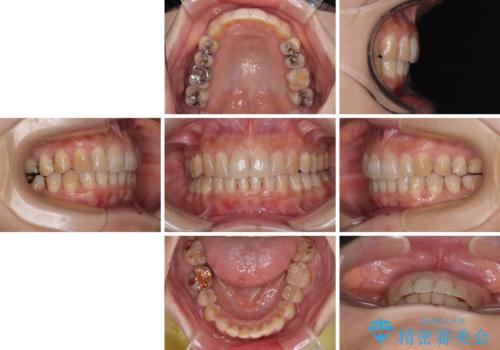

ディープバイトと前歯のデコボコ インビザラインによる矯正治療

- 前歯のディープバイトと叢生を気にして来院された患者様です。

目立ちにくい装置を希望されていたため、ワイヤー装置とインビザラインを提案したところ、インビザラインを希望されました。

下顎大臼歯が手前に倒れていたため、起き上がらせることで咬み合わせ高さを挙上し、ディープバイトと叢生を改善することとしました。

インビザライン特有の奥歯の噛みにくさが治療後半に発言しましたが、無事に終了させることができました。